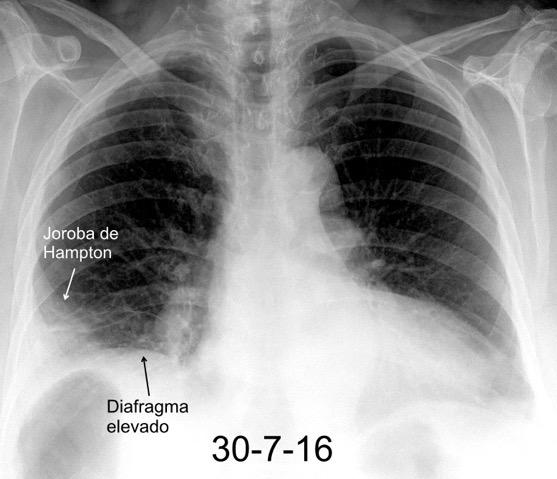

25. ELEVACIÓN UNILATERAL. TEP

Consolidación por Infarto pulmonar. (TEP)

Tromboembolismo pulmonar Diafragma elevado 20%